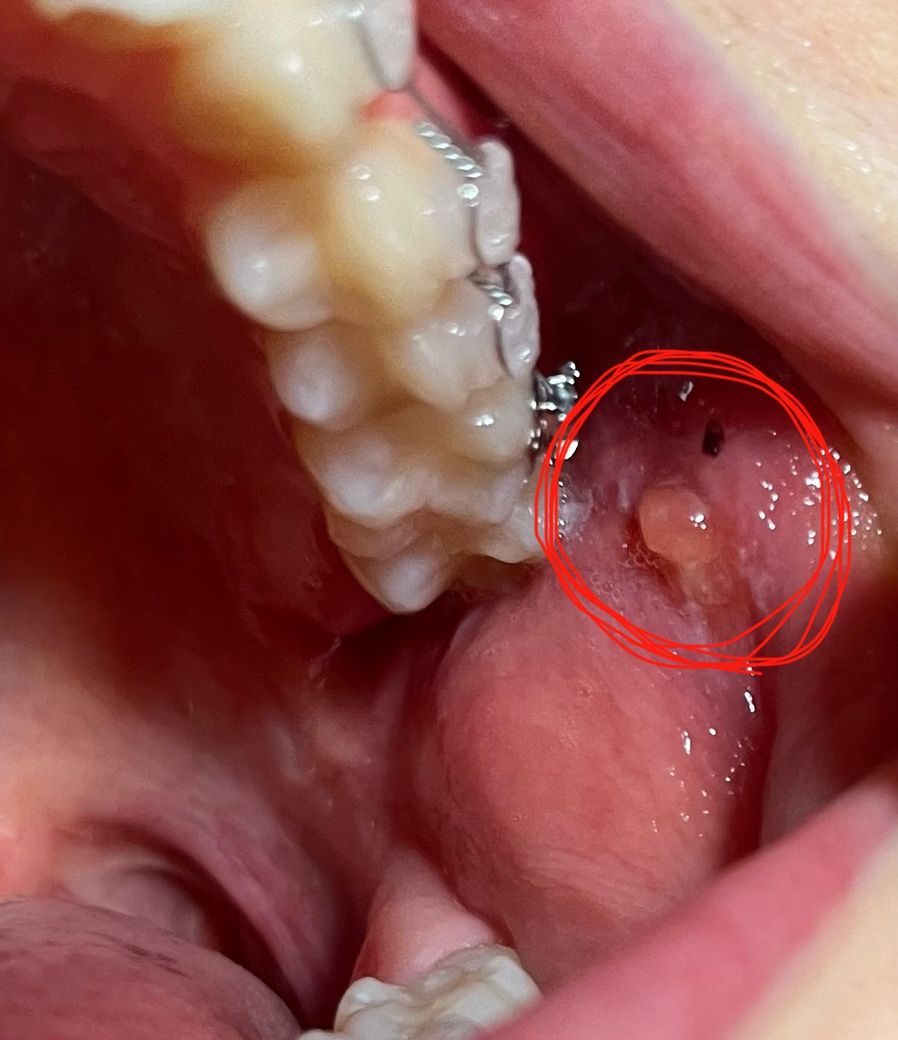

치아교정을 하고 다음날 보니 사진처럼 철사 닿는 곳 볼에 뭐가 튀어나왔습니다. 만지면 좀 아프고요. 짜면 없어질 줄 알고 짰더니 옆에 피만 나고 그대로입니다.

그대로 두면 사라질까요..? ㅠㅠ 무슨 약이라도 발라야 하나요.. 치과의사 선생님들 왜 그런 건지 제발 알려주세요. 부탁드립니다

교정장치에 자극을 받아 생긴 것입니다. 그냥두면 없어집니다. 교정장치에 껌 같이 붙히는 것이 있으니 치과에 가서 달라고 해서 붙히면 자극이 덜 갑니다.

볼에 교정기 등이 자극을 주면서 생긴 것으로 예상되며 억지로 짜지 마시고 치과에 가보시는 게 좋습니다.

교정장치에 볼살이 계속 자극을 받으면서 물집이 생긴거 같습니다. 큰 문제가 잇는건 아니고 터트리시면될것같습니다.

볼살이 자극을 받아 생긴 섬유종의 일종으로 보입니다. 치과 가서 처치 받으시기 바랍니다. 보통은 악성이 아니라면 절제합니다.